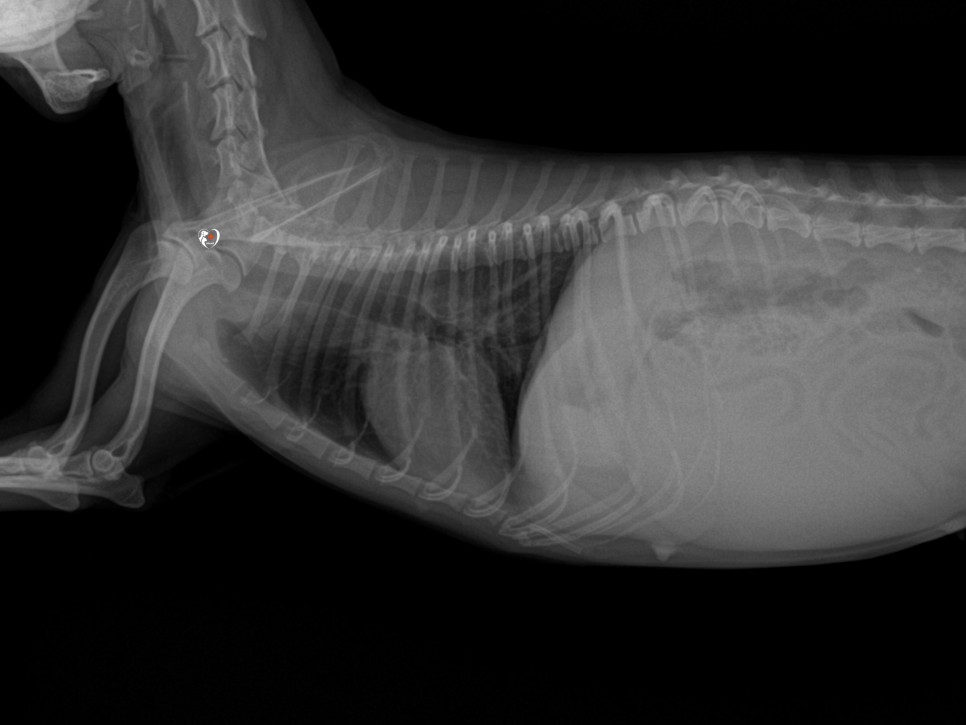

흉복부 X선 검사 결과는 양호했지만, 혈액 검사 상 빈혈 관찰이 되어 수혈을 먼저 한 후, 개의 자궁 축농증을 진행할 수 있었습니다.